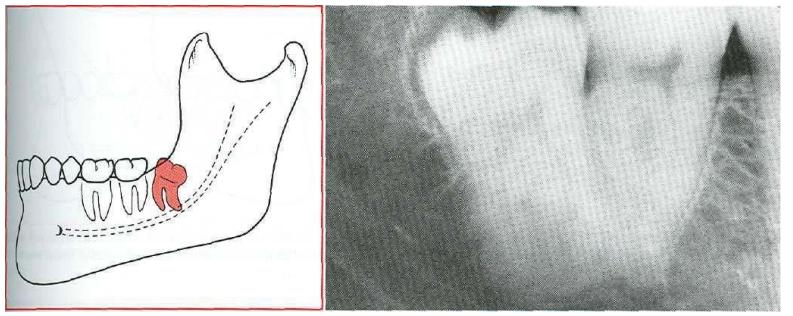

2-Distoangular 14

In the Distoangular impaction the long axis of the third molar is distally or posteriorly angled away from the second molar tooth

Fig .2: Distoangular impaction "From Contemporary Oral and Maxillofacial Surgery, chapter 9 Larry J. Peterson. Principles of management of impacted tooth p 195 '